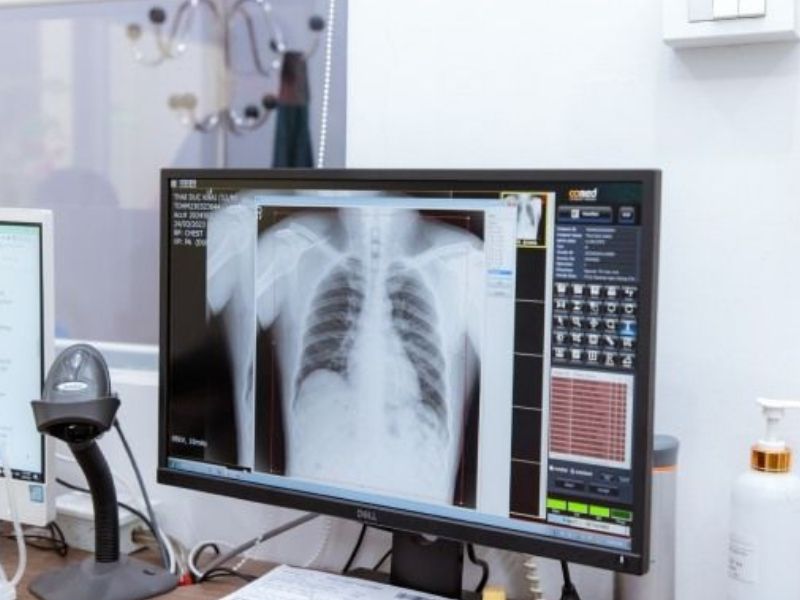

2.4.1. Chụp X-quang phổi

Chụp X-quang phổi là phương pháp đầu tiên được sử dụng trong việc phát hiện các tổn thương trong phổi.

• Ưu điểm: Thực hiện nhanh, chi phí thấp và có sẵn tại hầu hết các cơ sở y tế.

• Nhược điểm: Khó phát hiện những khối u nhỏ hoặc tổn thương ở các vị trí khó tiếp cận như đỉnh phổi.

X quang phổi giúp chuẩn đoán ung thư phổi